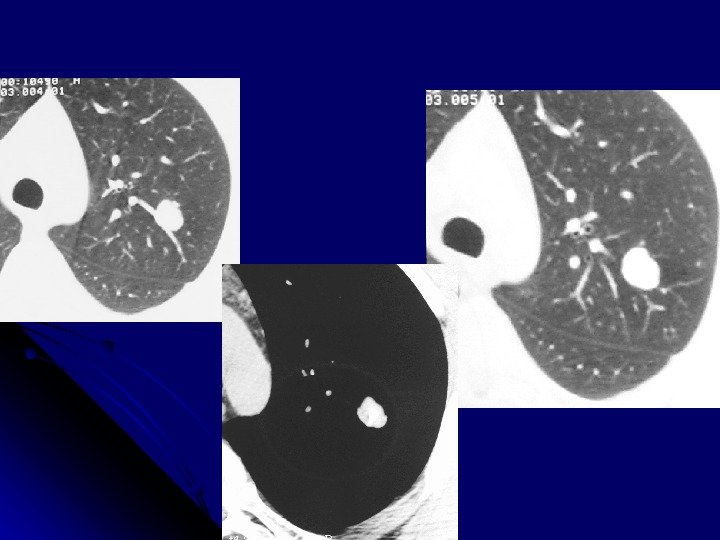

Аспергилема Форма округлая опухолевидная Кольцевидное просветление Гомогенное пристеночное образование на внутренней поверхности, окруженное с трех сторон полоской газа серповидной формы

Аспергиллема